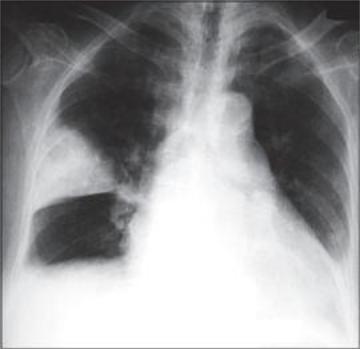

Рентгенография ОГК

263